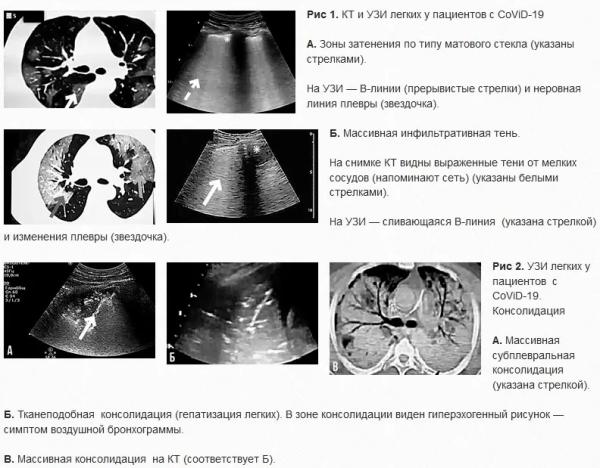

У пациентов с COVID-19 поражение в первую очередь находится в латеральных отделах легочных полей, субплевральной области. Кроме того, могут быть затронуты центральная лобулярная зона и альвеолы. Распределение поражения зависит от силы тяжести. Симптом воздушной бронхограммы на КТ также проявляется, когда на фоне консолидации видны заполненные воздухом бронхи. Ультразвуковая диагностика: основные признаки и механизмы Изменения на УЗИ соответствуют наблюдаемым на КТ. Ультразвуковая картина пневмонии, вызванной CoViD-19, в целом зависит от соотношения воздуха и жидкости в легких. В норме видны плевральная линия и горизонтальные А-линии и отмечается скольжение легкого. При интерстициальном легочном поражении наблюдаются вертикальные гиперэхогенные В-линии, характер которых меняется при ухудшении состояния (рис. 1). Расстояние между ними становится нерегулярным, и при прогрессировании заболевания визуализируются сливающиеся В-линии. Дальнейшая потеря воздушности приводит к формированию консолидаций, чаще всего наблюдаемых в субплевральной области (рис. 2). В-линии отходят от зон консолиации. При выраженной консолидации и тяжелом состоянии пациента легкое приобретает тканеподобную структуру, происходит так называемая гепатизация легкого, на фоне которой может быть виден гиперэхогенный рисунок — симптом легочной бронхограммы. Иногда может наблюдаться плевральный выпот (но он редко встречается при коронавирусной инфекции). Важно оценивать состояние плевральной линии: она становится неровной, появляются неравномерные утолщения, возникает ограничение и затруднение скольжения легкого. Важно, что у одного пациента могут быть практически все эти изменения — одновременно или в разные периоды заболевания: к примеру, в верхней зоне — А-линии, в средней — В-линии и небольшие зоны консолидации, в нижней — плевральный выпот.